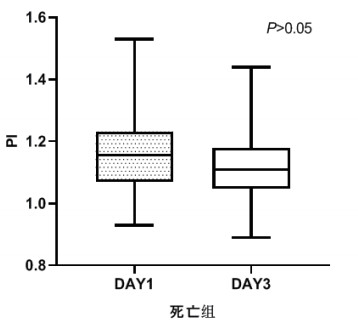

TCD参数组内治疗前后比较,生存组中无论PI还是RI在第3天时均较第1天有了明显下降,具有统计学意义(P < 0.05), 见图 2和图 3。死亡组在第1天和第3天测得的PI和RI值比较差异无统计学意义(P > 0.05),见图 4和图 5。可见生存组经治疗后脑循环较前改善,而死亡组治疗前后脑循环无明显改变。

| 图 4 死亡组第1天和第3天PI比较 Fig 4 Comparison of PI between the first day and the third day in the death group |